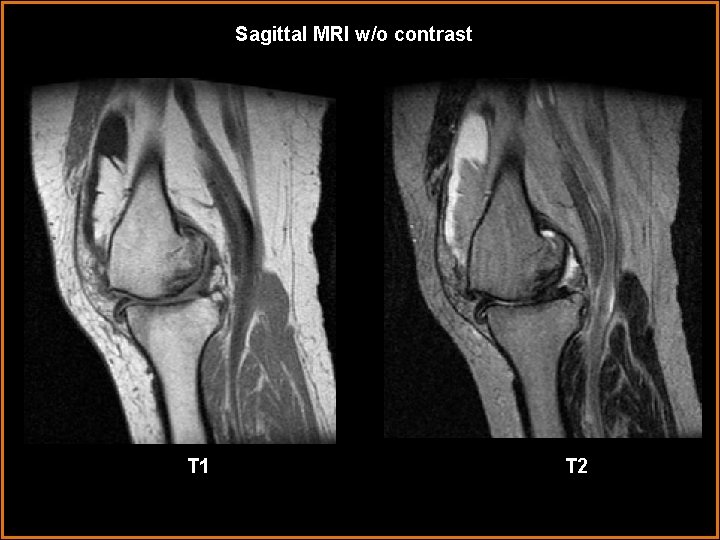

Sagittal MRI w/o contrast T 1 T 2

Findings and Differentials Findings: Plain radiographs: Severe degenerative changes of the left knee, greatest in the medial compartment. There is joint space narrowing with osteophyte formation at the joint margins and subchondral cyst formation. A moderate-to-large suprapatellar joint effusion and/or synovial proliferation is present. MRI: There is a moderate joint effusion with extensive proliferation of lipomatous synovium in the suprapatellar recess of the joint. Extensive degenerative changes as seen on the plain radiographs are again noted. In addition, extrusion of the medial meniscus is present. Differentials: • Lipoma arborescens • Synovial Chondromatosis • Pigmented Villonodular Synovitis

Discussion Lipoma Arborescens: Rare benign condition that typically occurs in the 5 th to 7 th decades of life. It is characterized by replacement of subsynovial tissues by mature fat cells and represents a nonspecific reaction to trauma or inflammation. It is typically monarticular and is seen to occur most commonly in the suprapatellar recess of the knee. Patients most commonly present with long standing joint pain. Diagnosis can be made on MRI as the fatty proliferation exhibits the same signal as subcutaneous fat on all sequences. It is frequently seen in association with osteoarthritic degenerative changes. Synovial Chondromatosis: Benign condition typically occuring between 3 rd and 5 th decades of life. Occurs in men twice as commonly as women. It is characterized by synovial proliferation resulting in formation of cartilaginous intra-articular loose bodies. Over time, these cartilaginous nodules may calcify. This condition is also monarticular and most commonly seen in the knee. Patients typically present with joint pain and limited joint motion. Patients typically have joint effusion or fullness on plain film. Marginal erosions at the joint may occur. Secondary arthritic changes are usually a late findings after longstanding presence of intra-articular loose bodies. Non-calcified cartilage loose bodies are typically isointense to muscle on T 1 imaging and hyperintense on T 2. Areas of calcification will be low signal on T 1 and T 2.